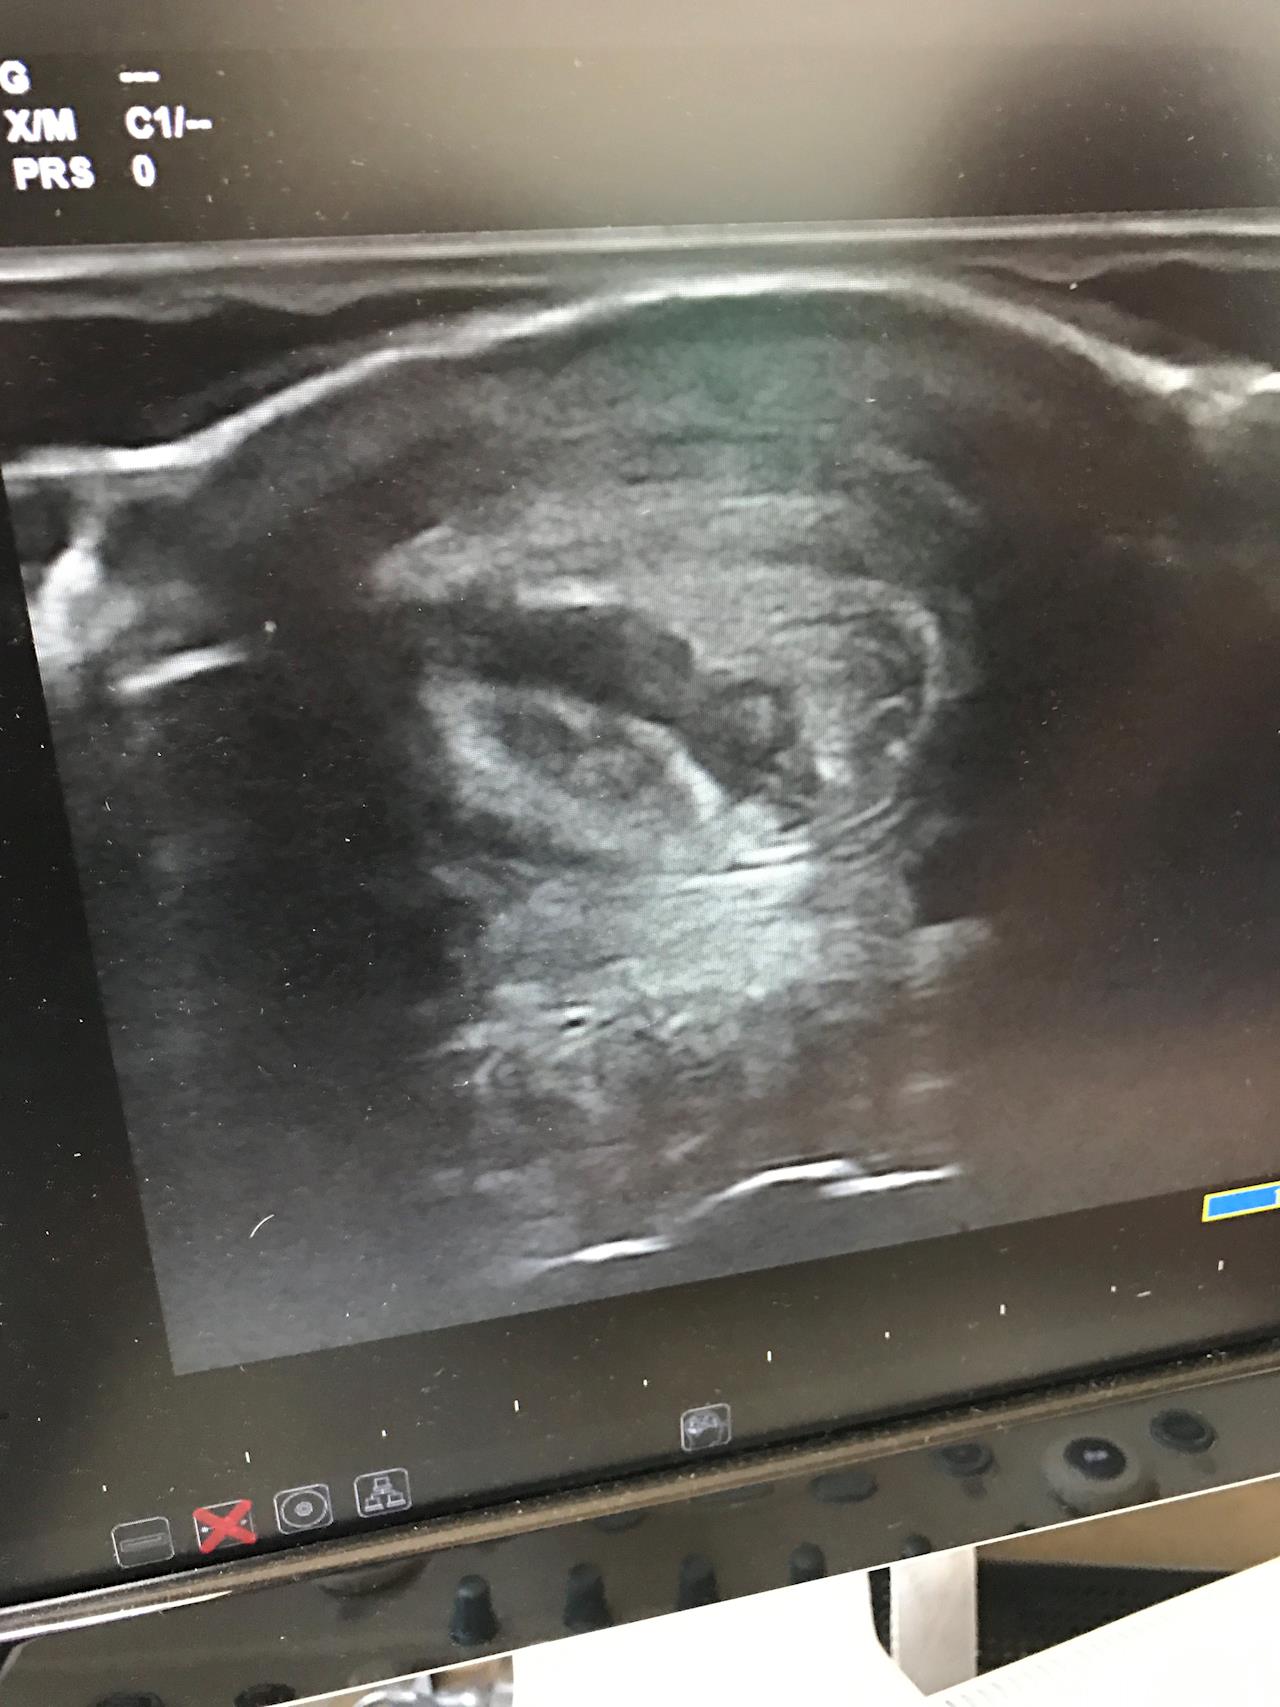

Main image

Jafa all loaded up and off to the vet, let's hope for the best,

We have added a scan of the leg and the image shows a black area through the tendon, this mark is the dogs tooth pearcing the tendon.